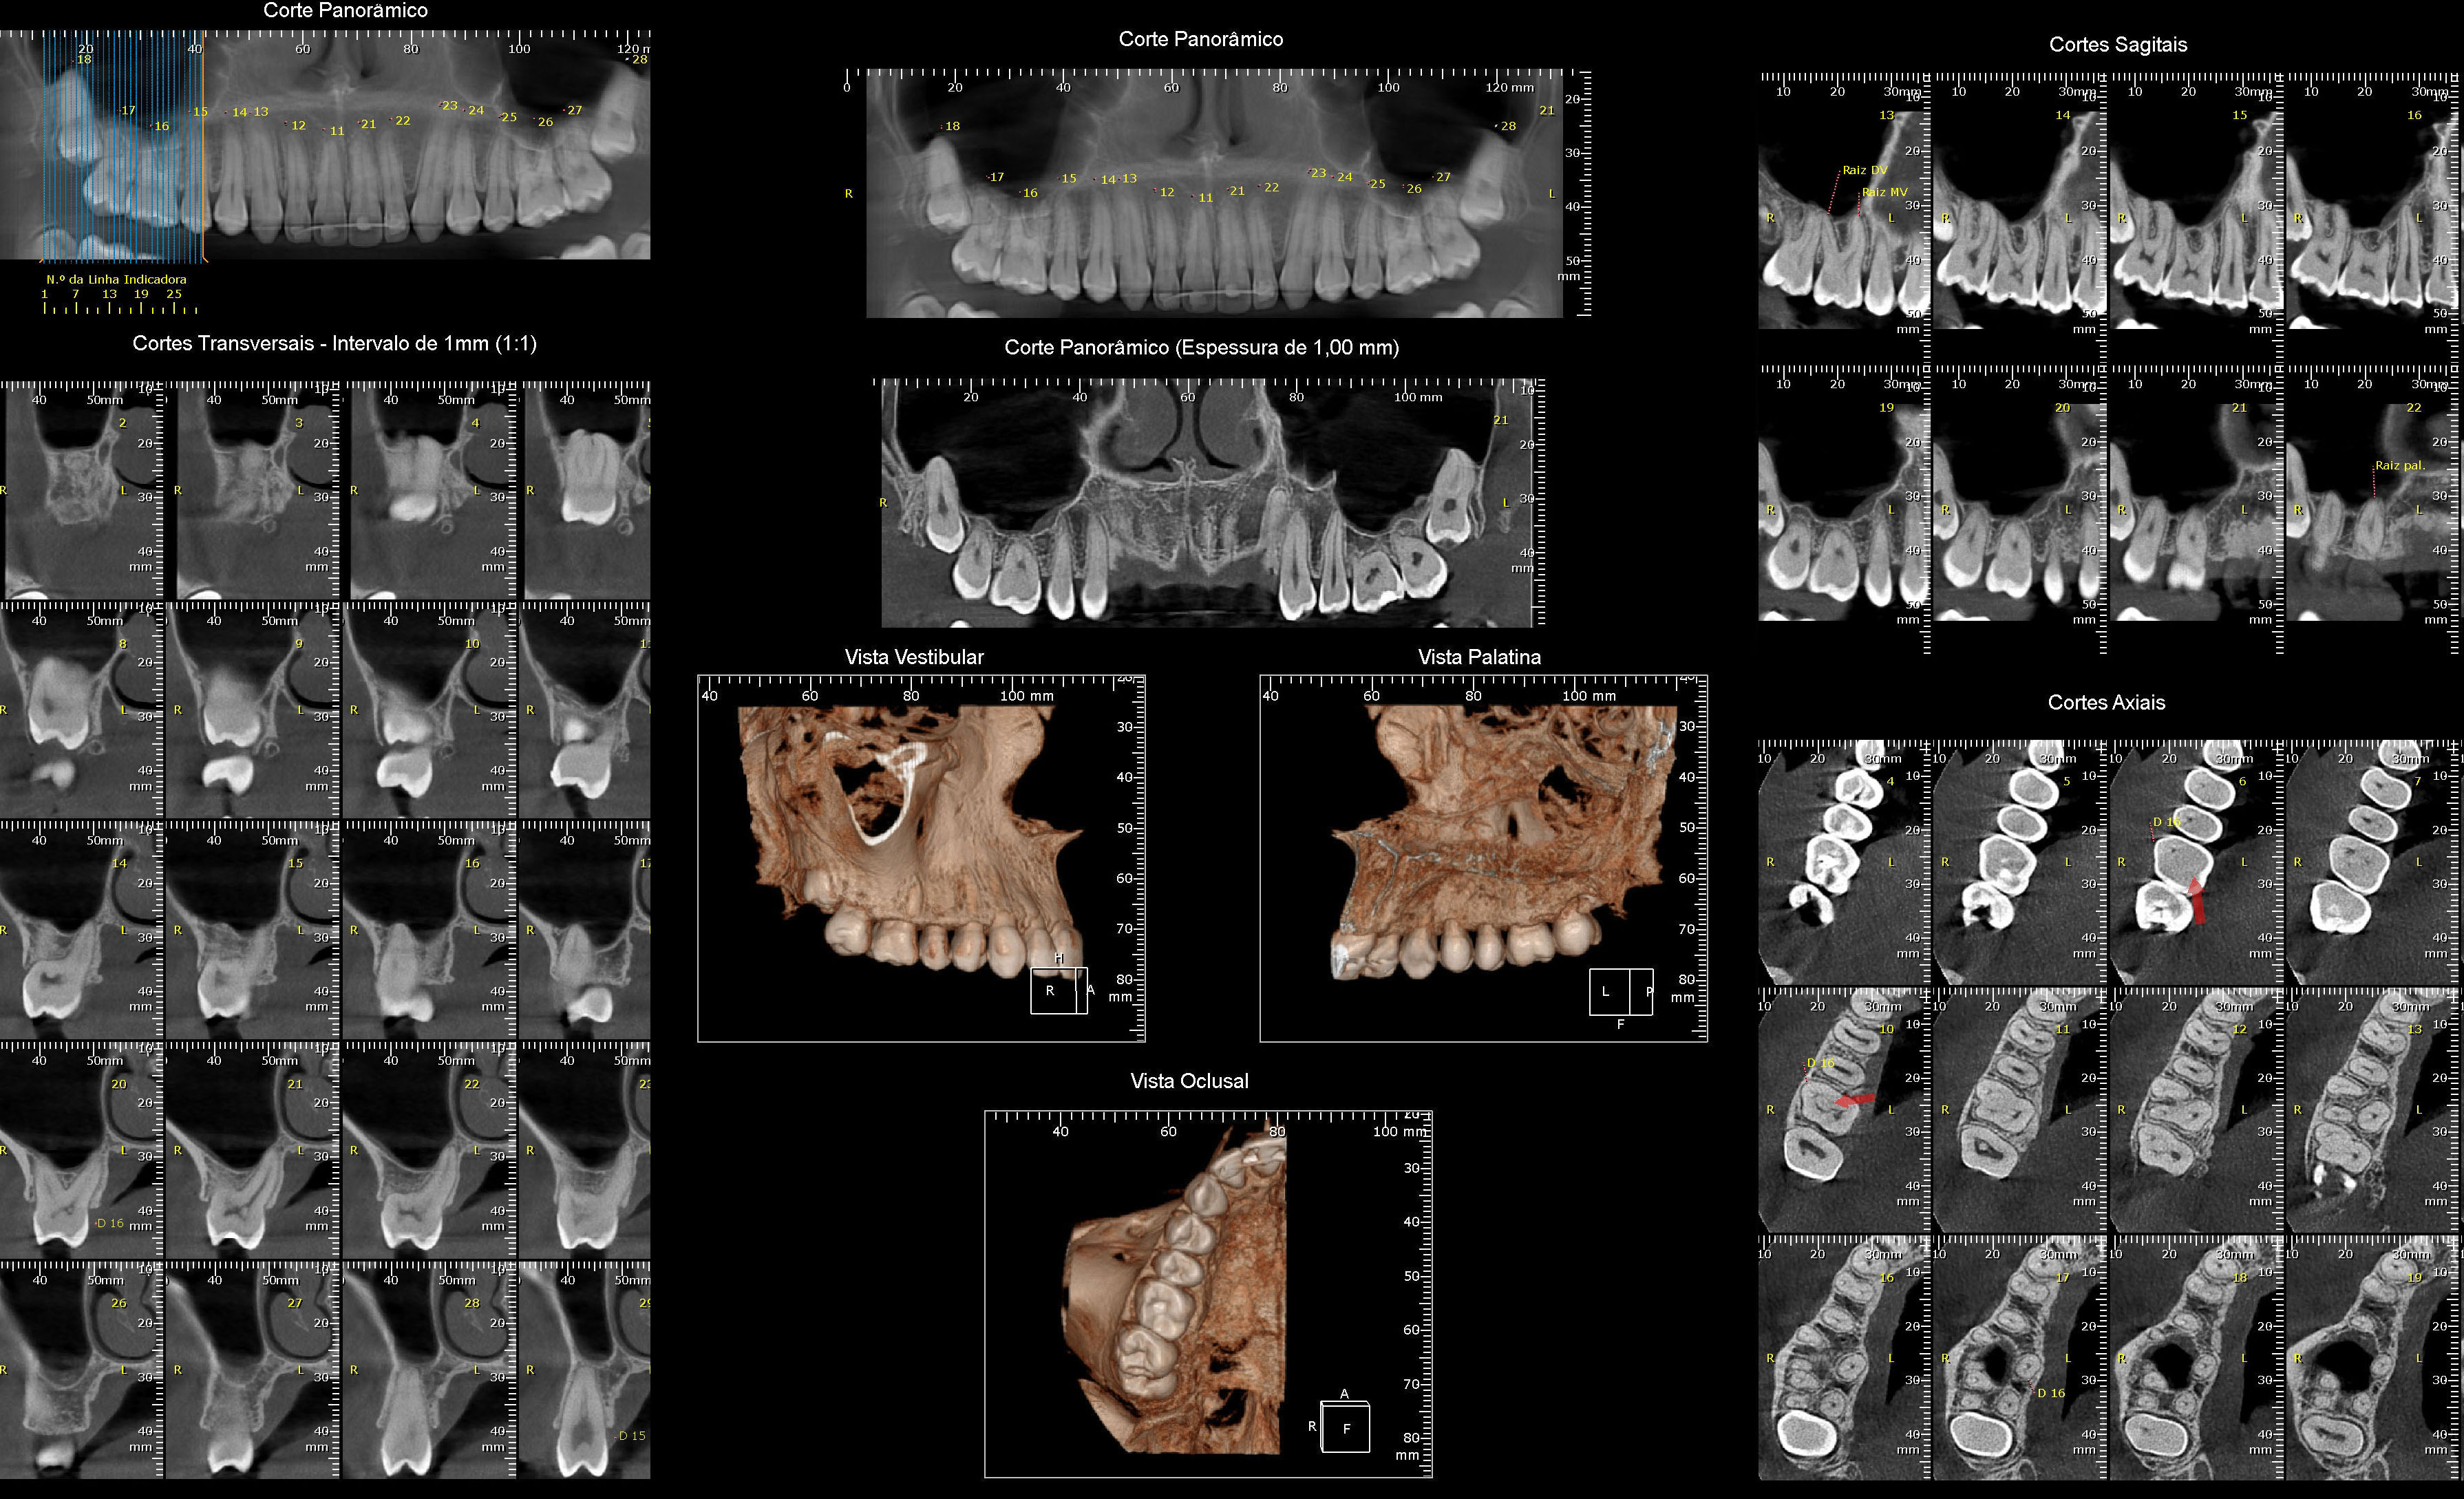

Radiografias Digitais

- Raio X Panorâmico

Documentações

- Radiografias Digitais com Laudos e Análises